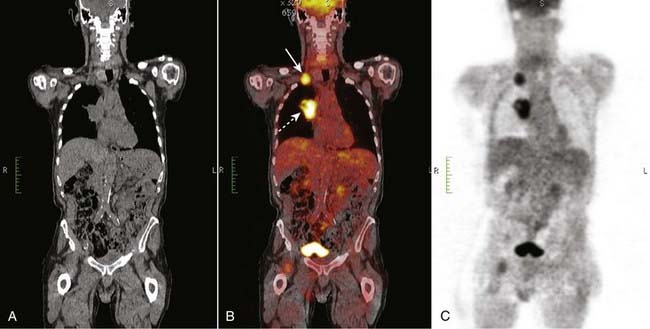

image FDG avid lesions are those that show abnormally increased uptake of the radiopharmaceutical (Figs. 29 and 30).

image

Figure 30 Positive PET scan, bronchogenic carcinoma with metastases.

A large right hilar mass (dotted white arrow) is FDG avid and represented a bronchogenic carcinoma (B). Less evident was a right supraclavicular lymph node metastasis (solid white arrow). PET scans are especially helpful in detecting occult metastases.